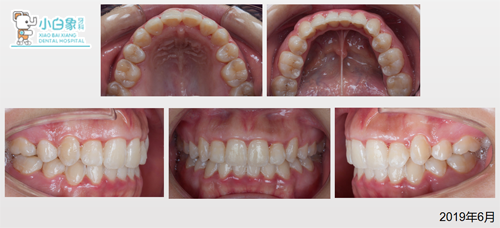

治疗前面相

检查

治疗前后对比